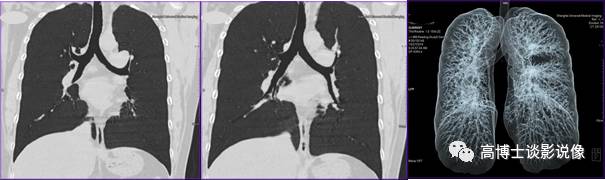

三、肺气道重建

双侧斜冠状位MinP(最小密度投影)显示气道情况。使用VRT虚拟成像整体显示气道情况(密实或透明化)。了解气道有无狭窄以及狭窄的位置、程度、范围、原因等,能无创性评价气道的狭窄,尤其适用于支气管纤维镜不能通过者;了解气道的顺应性等功能情况及气道狭窄周围肺组织的情况;气道狭窄支架置入术后,了解支架的通畅情况。